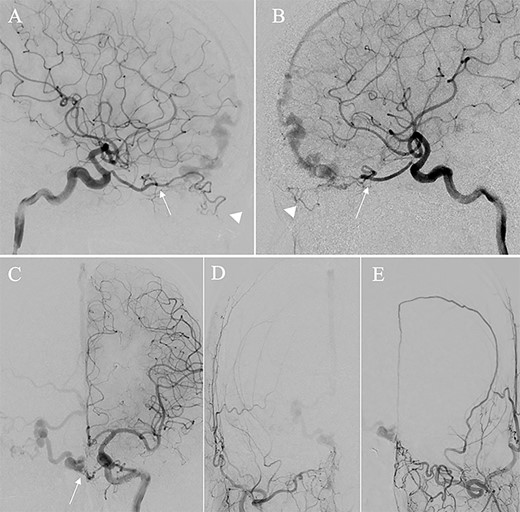

A patient in their 70s with extracranial lymphoma was incidentally found to have ACF–dAVF via head computed tomography and magnetic resonance angiography. Digital subtraction angiography (DSA) confirmed ACF–dAVF with multiple feeding branches, arising from bilateral OphAs, distal IMAs and the left middle meningeal artery (MMA), with cortical venous reflex (Borden type III, Cognard type IV) (Fig. 1). At the patient’s request, we chose endovascular, rather than surgical, treatment. We injected a 20% N-butyl-2-cyanoacrylate (NBCA)–lipiodol mixture into the fistula through bilateral ethmoidal arteries and the left MMA after we placed coils at the terminal branch of the right OphA. However, we could not achieve full penetration into the fistulous connections because of pressure secondary to high flow from the IMA branches, which resulted in incomplete obliteration (Fig. 1). Four months later, we repeated TAE by temporarily reducing nasal blood flow by inserting gauze infiltrated with xylocaine and epinephrine into the nasal cavities. After introducing the guiding catheter, an endonasal surgeon inserted X-ray-detectable surgical gauze infiltrated with 1% xylocaine and epinephrine (1:10 000) into bilateral nasal cavities using a nasal speculum, while paying full attention to avoid damage to the nasal mucosa. Then, we confirmed that the gauzes were placed in appropriate locations in the upper nasal cavity under fluoroscopic guidance. Immediately after insertion, we were able to confirm decreased blood flow from the IMA using DSA (Fig. 2). After this procedure, we navigated a DeFrictor Nano Catheter (Medico’s Hirata, Osaka, Japan) into the terminal branch of the OphA, which was connected to the dorsal nasal artery. Even though there was still a distance from the tip of the microcatheter to the shunt pouch, the NBCA reached the shunt point and penetrated the venous portion (Fig. 3). Follow-up DSA demonstrated complete obliteration of the ACF–dAVF, and blood flow in the nasal mucosa from the IMA branches recovered normally (Fig. 4).

Right (A) and left (B and C) internal carotid artery angiography before initial treatment showing ACF–dAVF with feeding arteries arising from branches of the OphAs; ethmoid artery (arrow) and dorsal nasal artery (arrowhead) (D and E). Bilateral external carotid artery angiography before initial treatment, anteroposterior view, showing the ACF–dAVF fed by bilateral distal internal maxillary arteries and the left middle meningeal artery.